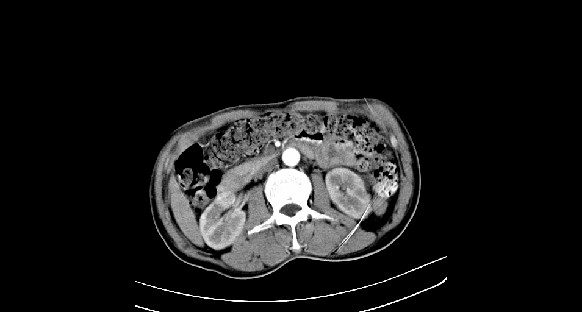

男性,70岁,体检b超发现左肾占位,请各位战友发表一下观点

左肾有两个病灶,且较大的病灶内可见点状钙化灶,增强扫描边缘也是呈渐进性强化,中央部分未见明显强化

肾癌较肾aml可能大,建议mri,若t2明显高信号者则肾癌基本诊断明确。